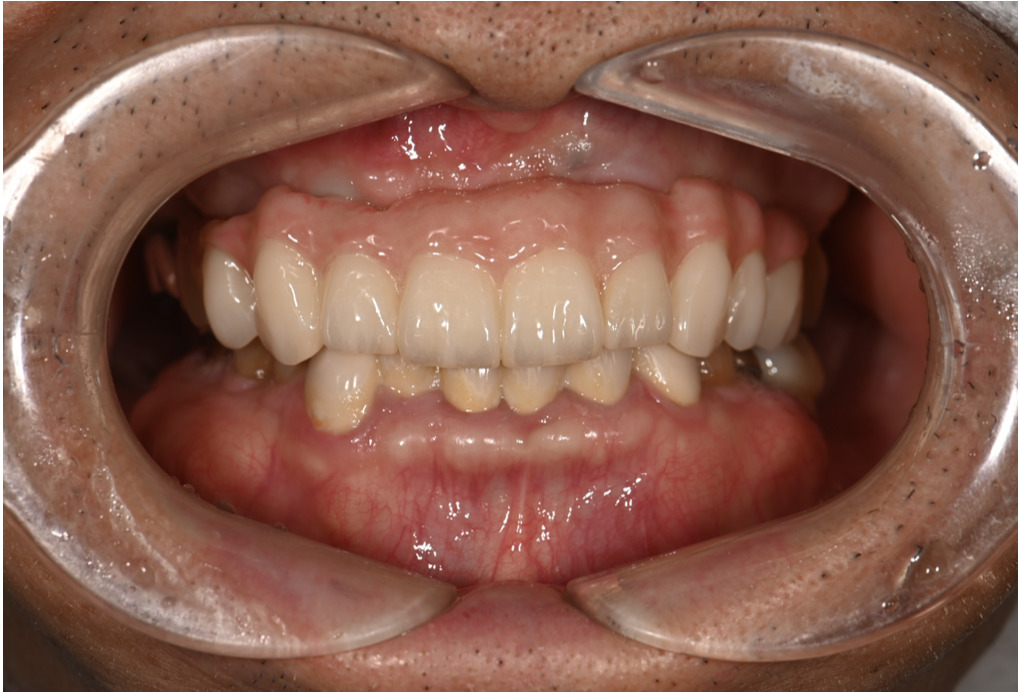

| 主訴 | 歯がグラグラして噛めない |

|---|---|

| 治療内容 | 上顎、下顎に対するインプラント治療 |

| 治療期間 | 1日 |

| 治療費 | 409万2千円 |

| 治療 リスク | 最終的な歯が入るまでは仮歯になります。 |